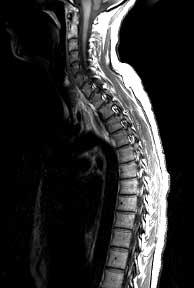

T1 sagittals pre-gad